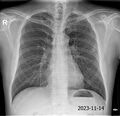

1. X-RAY 촬영. 전면 및 측면 두 장

1. 오늘 찍은 X-RAY보면서 괜찮다. 폐렴 없다.